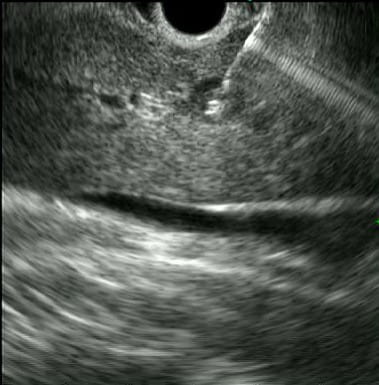

The objective of this study is to identify early markers of pancreatic cancer and other pancreatic abnormalities that are detectable before any symptoms of disease are apparent. The study enrolls individuals considered to be at high risk for developing pancreatic cancer due to genetic mutations and/or family history. It works in conjunction with regularly scheduled, standard of care Endoscopic Ultrasound (EUS) and MRI procedures. Annual surveillance with one of these procedures is generally considered to be standard of care for individuals at high risk for pancreatic cancer.